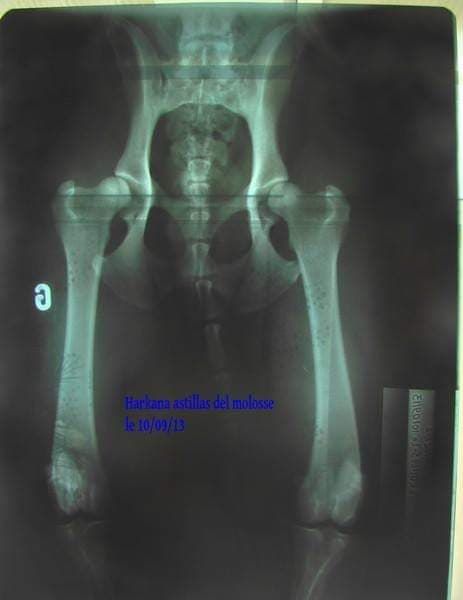

radiographie officielle faite